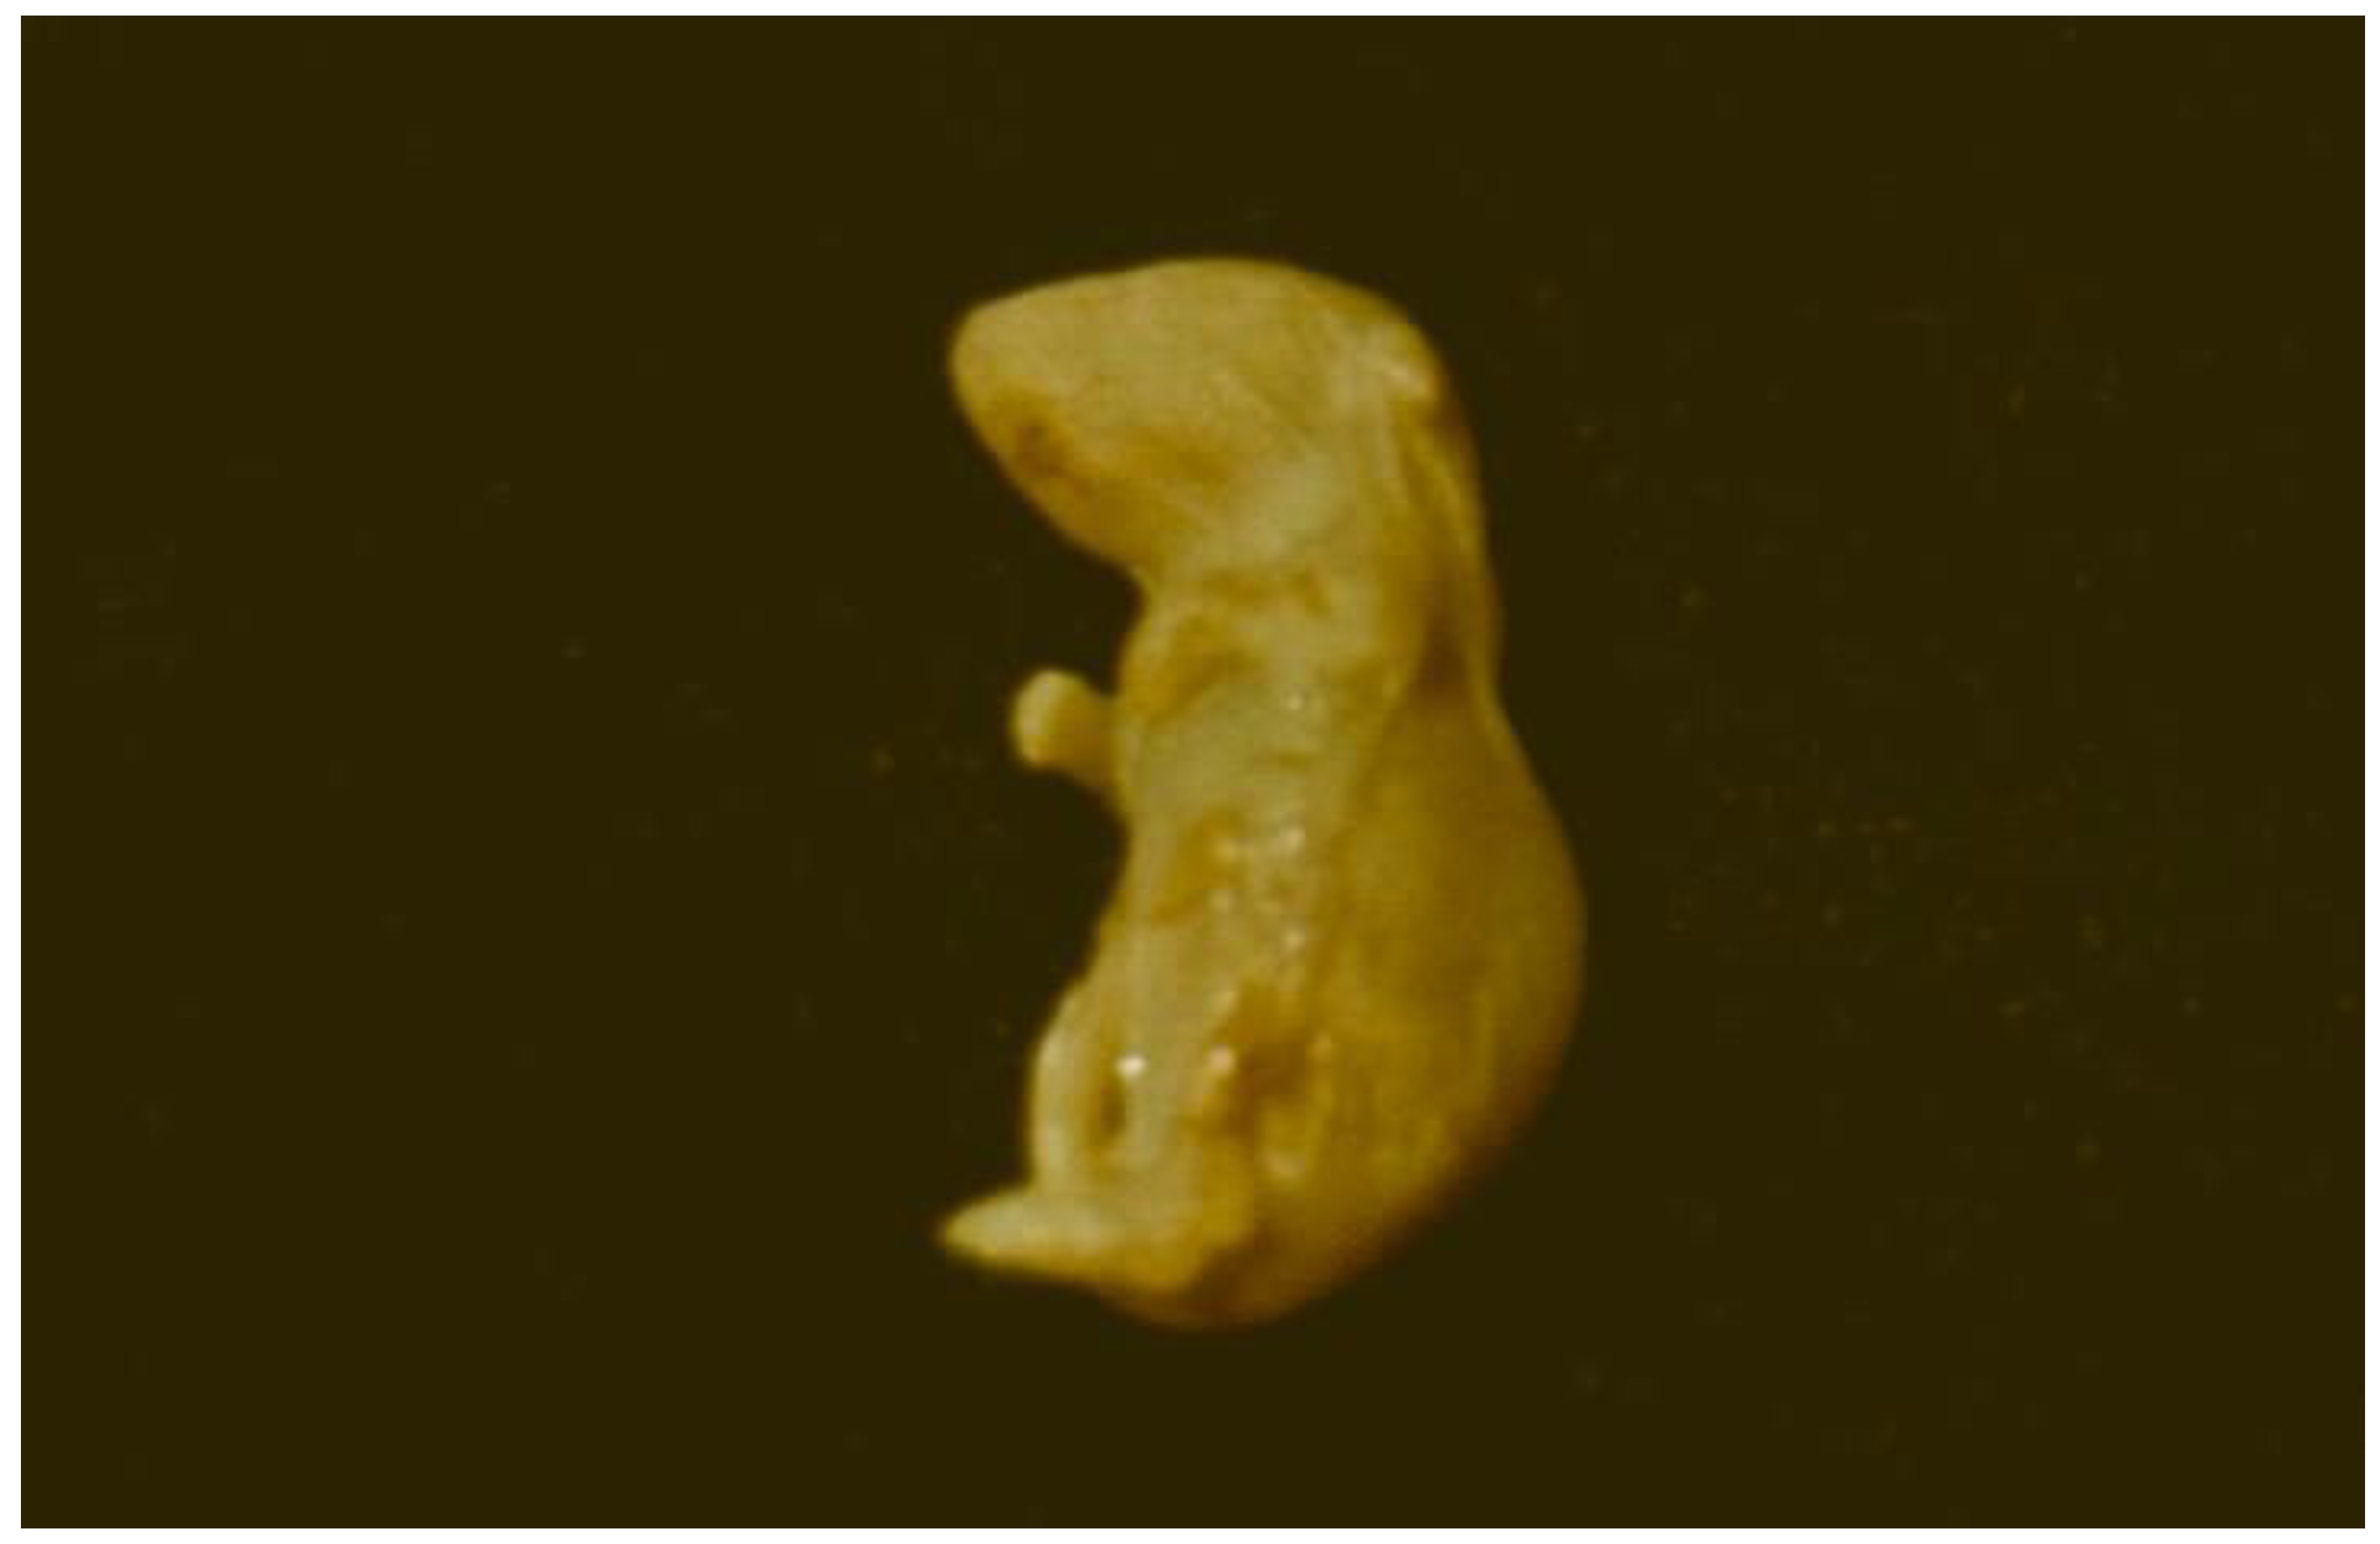

- Pósa, R., Magyar, T., Stoev, S.D., Glávits, R., Donkó, T., Repa, I., Kovács, M. (2013). Use of Computed Tomography and Histopathologic Review for Lung Lesions Produced by the Interaction Between Mycoplasma hyopneumoniae and Fumonisin Mycotoxins in Pigs. Vet. Pathol., 50(6), 971-979.

- Pósa, R., Stoev, S.D., Kovács, M., Donkó, T., Repa, I., Magyar, T. (2016). A comparative pathological finding in pigs exposed to fumonisin B1 and/or Mycoplasma hyopneumoniae, Tox. Ind. Health, 32, 6, 998-1012.